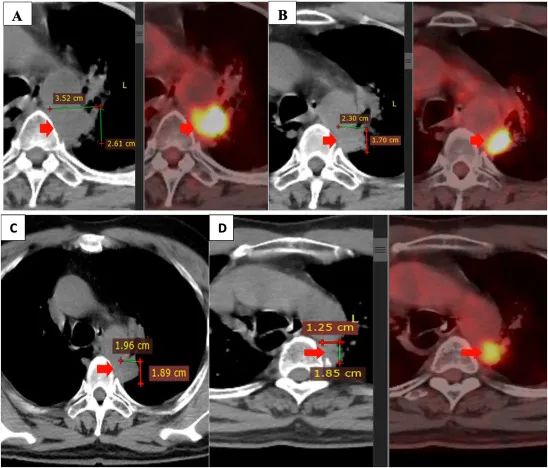

注:聯合治療前后的原發性腫瘤。原發腫瘤在二線治療(4 個周期的 alimta,卡鉑,可瑞達)后進展(A)。原發腫瘤在治療結束時與自體 NK 細胞療法,吉西他濱,貝伐珠單抗(B),3 個月后(C),6 個月(D)組合減少。

患者在 4 至 5 個月內、每 3 周內和在此期間每 3 周接受 6 個療程的自體 NK 細胞輸注。在此期間,患者在第 1 天和第 8 天(每 3 周 2 個周期)接受阿瓦斯?。?/span>400mg,每 3 周 2 個周期)聯合吉西他濱(1800mg)治療,干咳和胸痛癥狀消失。患者飲食良好,生活質量顯著提高。聯合治療期間未觀察到明顯副作用,肝腎功能評估在正常范圍內。

2021 年 3 月和 2021 年 9 月進行的 PET/CT 掃描顯示,與聯合治療前相比,原發腫瘤的大小顯著縮小。此外,兩側均未發現縱隔或鎖骨上淋巴結。